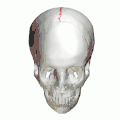

Sagittal suture

The sagittal suture, also known as the interparietal suture and the sutura interparietalis, is a dense, fibrous connective tissue joint between the two parietal bones of the skull. The term is derived from the Latin word sagitta, meaning arrow.

Animation. Sagittal suture shown in red. -